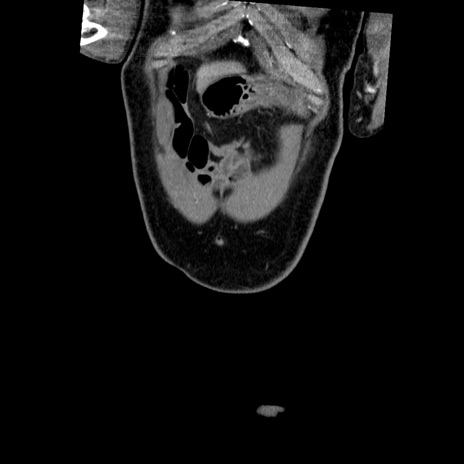

症例22(冠状断像)

【症例】50歳代男性

【主訴】腹痛

【現病歴】AVMからの被殻出血のため回復期リハ病棟入院中。 本日午後3時頃急に下腹部痛が出現した。

【既往歴】AVM、被殻出血、虫垂炎、高血圧

【身体所見】意識晴明、左半身不全麻痺、会話の理解は良好、36.5°C、腹部:膨隆、全体に板状硬、下腹部正中に圧痛点あり、反跳痛-、筋性防御不明、右下腹部にope scar

【データ】WBC 9400、CRP 0.06